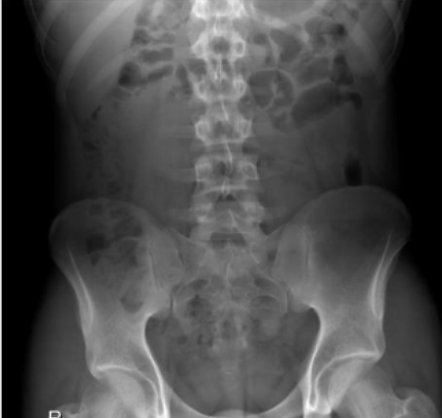

Identify parts of pelvis (6)

yes